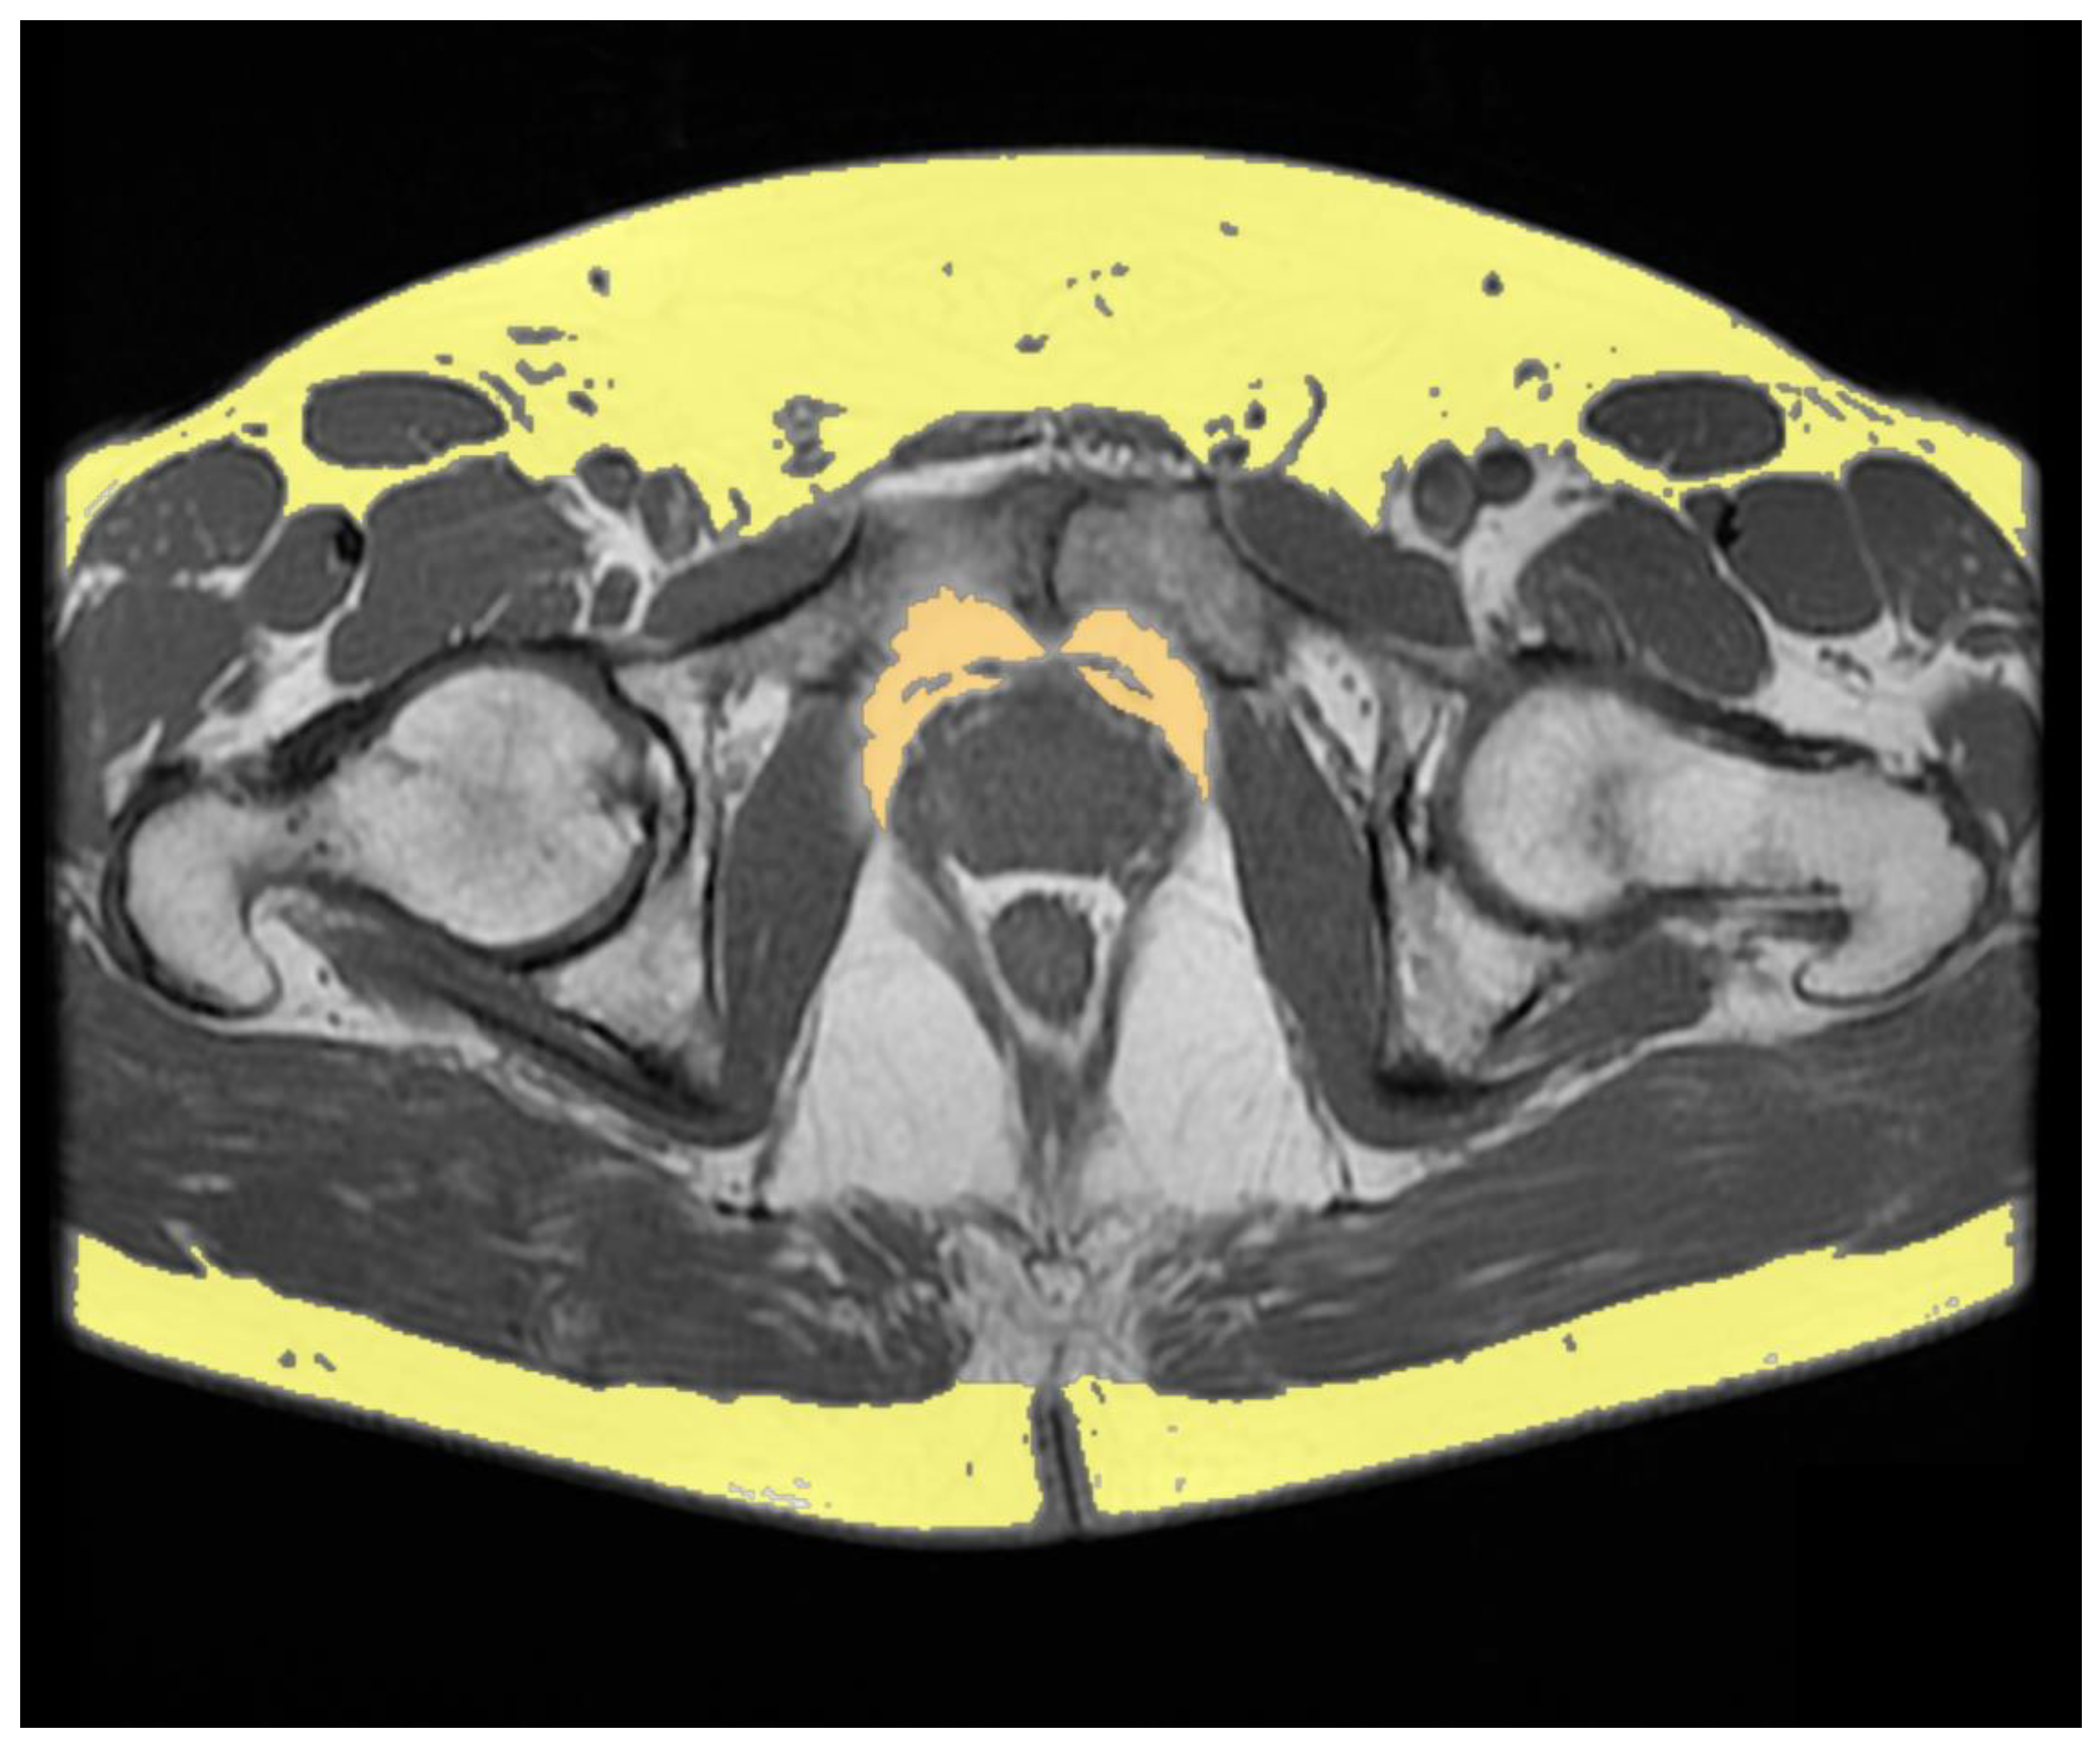

Androgens play an active role in body composition in men. Indeed, a positive correlation has been found between serum testosterone concentrations and lean mass together with a negative correlation with fat mass [1]. Testosterone replacement therapy determines an increase in lean body mass and a decrease in fat mass in hypogonadal men [2,3]. Surgical androgen deprivation or medical castration were the basis for treatment of advanced prostate cancer [4]. The new cytotoxic and androgen receptor-targeted therapies have demonstrated a survival benefit in association with androgen deprivation [5]. Considering that androgens are important for the homeostasis of different organ systems, their use is related to a number of harmful effects [6]. One of the side effects of androgen deprivation therapy (ADT), even for short term treatment, is an increase of fat mass [7,8]. The absence of androgen-related hormones changes the lipid composition of tissues and decreased insulin sensitivity, resulting in the promotion of an obese-like phenotype [9,10]. A body mass index (BMI) greater than 30 kg/m2 defines obesity, but it does not provide information on body composition such as the quantity of the different adipose tissue compartments [11,12]. Fat compartments can be distinguished by computed tomography (CT) and magnetic resonance imaging (MRI), non-invasive imaging techniques for qualitative and quantitative analysis of tissues (Figure 1 and Figure 2) [13,14,15,16,17].

Figure 2.

Axial T1-weighted MRI image showing periprostatic adipose tissue segmented in orange and SAT segmented in yellow.